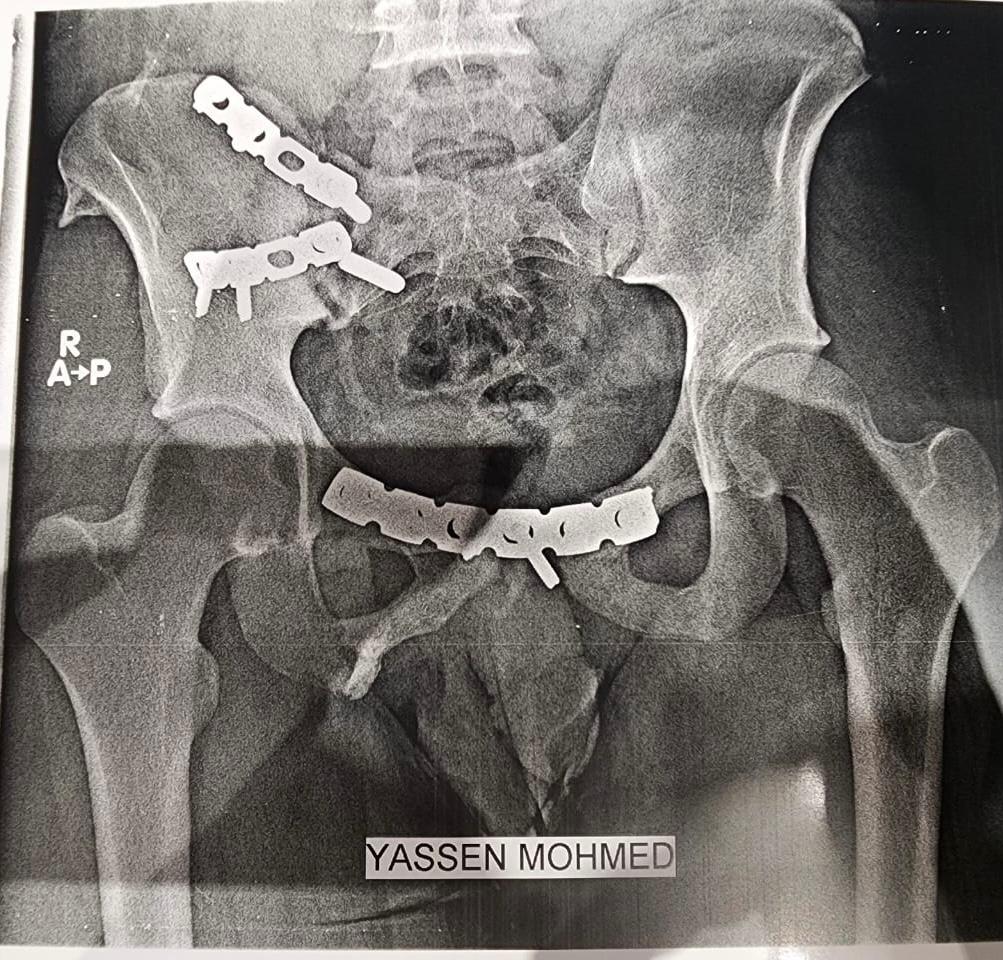

ياسين محمد أمين العمر:١٧ عامًا اصيب بكسر غير ثابت متفتت بالحوض يناير ٢٠٢٣